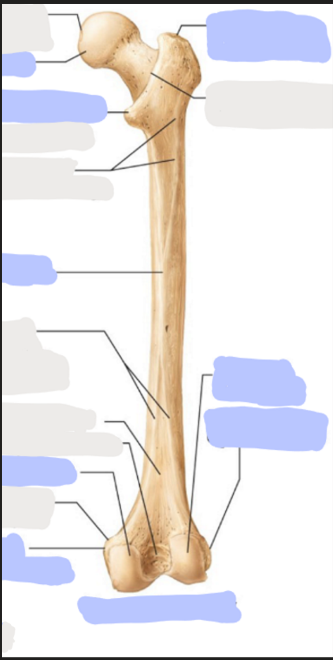

What is this picture of?

Posterior view of the Right Femur

What is here?

Where is the Head of the Femur?

What is here?

Where is the Lesser Trochanter of the Femur?

What is here?

Where is the Linea Aspera of the Femur?

What is here?

Where is the Medial Condyle of the Femur?

What is here?

Where is the Medial Epicondyle of the Femur?

What is here?

Where is the Greater Trochanter of the Femur?

What is here?

Where is the Lateral Condyle of the Femur?

What is here?

Where is the Lateral Epicondyle of the Femur?